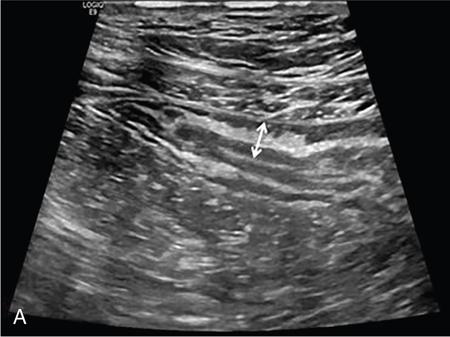

Kavita Saggar, Archana Ahluwalia, Devinder Pal Singh Dhanota, Geetika Khanna, Chander Gupta Inflammatory bowel disease (IBD) represents chronic idiopathic inflammation of the gastrointestinal [GI] tract. The common subtypes are Crohn’s disease, ulcerative colitis (UC) and indeterminate colitis (Fig. 7.11.1). Approximately 20%–25% of patients present in childhood or adolescence. Of these, nearly two-thirds of cases are caused by Crohn’s disease with an incidence of 4.56 per 1000,000 children (Fig. 7.11.2). IBD can affect any portion of the GI tract; however, children have a much higher incidence of small bowel and colonic involvement (Table 7.11.1). Currently, there is no single diagnostic test for the evaluation of IBD. Diagnosis is based on a combination of history, physical examination, serum inflammatory markers, endoscopy, histopathology and imaging. A host of imaging modalities is available for the evaluation of IBD in children. Traditionally, barium fluoroscopic studies, namely small bowel follow-through or small bowel enteroclysis (SBE) were used. However, barium studies depict only the mucosal abnormalities and do not evaluate the extraluminal extent of disease. Ultrasonography (US) is increasingly being used in the workup of patients with IBD. Small intestine contrast ultrasound (SICUS) and contrast-enhanced ultrasound (CEUS) are used for evaluation of IBD. CEUS requires intravenous administration of microbubble contrast such as Sonovue, and SICUS requires small bowel adequate luminal distension with ingestion of an iso-osmolar contrast agent such as polyethylene glycol. A recent meta-analysis of 33 studies showed that CEUS had better accuracy than US, CT and MR for the detection of inflammation and differentiation of fibrotic and inflammatory strictures. However, the extent of the disease was better evaluated by CT and MR. Currently, computed tomography enterography (CTE) and magnetic resonance enterography (MRE) have emerged as the most effective tools for imaging small bowel in patients with IBD. CTE and MRE can accurately depict the spectrum of imaging findings related to severity, extent and complications of IBD and thereby help in guiding management and assess the response to treatment. MRE is an attractive imaging modality due to lack of ionizing radiation, inherent multiplanar capability and excellent soft tissue contrast resolution. In addition, dynamic/cine imaging allows assessment of peristalsis and accurate identification of the diseased segment. The major disadvantage of MRE is high cost, lower spatial and temporal resolution and long examination time. Crohn’s disease is a transmural granulomatous disease that can affect any part of the GI tract from the oral cavity to anus, often involving multiple discontinuous segments of bowel. Patients have a genetic predilection to develop an abnormal immunologic response to environmental factors including food and gut flora, leading to a chronic inflammatory response. Small bowel is the major site of involvement. Terminal ileum is the most common location which is involved in approximately one-third patients. The colon is affected in 50% patients. In 15%–20% cases, there may be isolated involvement of the colon without affecting the small bowel. The clinical importance of small bowel Crohn’s disease is the impact that a diffuse small bowel disease is expected to have on child’s growth and development. Thus, objective evaluation of small bowel is essential in differentiating from other enteropathies and in directing the management of patients with IBD. Two methods used for imaging small bowel with barium using fluoroscopy are standard small bowel follow through (SBFT) and SBE. Small bowel evaluation with barium has long been considered the most common, noninvasive, inexpensive and easily accessible radiological method, but it has been replaced by cross-sectional imaging. In the current scenario, the only indication of barium studies is when CTE or MRE cannot be done because of nonavailability or are not feasible. Ultrasound is being increasingly used to assess the activity of Crohn’s disease, especially in paediatric patients. Greyscale ultrasound allows morphologic assessment of bowel wall and mesentery. Normal small bowel loops are easily compressible with the transducer and the wall thickness is <2 mm. The bowel loops show regular peristalsis and are mobile. Colour Doppler shows minimal intramural or perienteric vascularity. The salient sonographic features of Crohn’s disease are: There is marked concentric or eccentric bowel wall thickening [>2.5–3 mm]. The mural echogenicity depends upon the degree of inflammation and fibrosis. In the acute phase, mural stratification is maintained (Fig. 7.11.3A and B). In patients with long-standing disease, a target or pseudo-kidney appearance may be seen. In long-standing burnt-out disease, there is submucosal fat deposition. The actively inflamed bowel segments show increased vascularity on Doppler ultrasound (Fig. 7.11.4A and B). CEUS with microbubbles can objectively assess the disease activity. A stricture is seen as a segment of bowel wall thickening with apposition of the luminal surfaces. There is persistent luminal narrowing with variable degree of upstream dilatation and hyperperistalsis. Doppler imaging reveals hyperemia in strictures with an active inflammatory component. Fibrotic strictures do not demonstrate increased blood flow. A major advantage of ultrasound is real-time imaging which allows the evaluation of bowel peristalsis. The diseased segments of the bowel (inflamed or fibrotic) show reduced peristalsis and often appear fixed in position. Mesenteric inflammation is commonly seen in active Crohn’s disease. Sonography reveals thickening of mesentery with heterogeneous echogenicity due to oedema. Doppler ultrasound shows increased vascularity due to engorgement of vasa recta. Fibrofatty proliferation of mesentery seen in chronic disease appears as abnormally thickened echogenic fat that displaces the bowel loops. Reactive mesenteric lymph nodes (up to 1.5 cm) can be seen in the active inflammatory phase of Crohn’s disease. These appear as hypoechoic round or oval structures with preserved fatty hilum. Sinus tracts and fistula often arise from or just proximal to a strictured segment and appear as linear areas of altered hypoechogenicity extending from serosal surface of gut. There may be tethering and/or angulation of the affected bowel segment. Abscesses are discrete well-defined fluid collections with internal debris, septation or nondependent echogenic gas. Colour Doppler reveals peripheral hyperemia with absent blood flow centrally. Ultrasound may be falsely negative if an abscess contains a large amount of air and can be mistaken for an air-filled bowel loop. Both CTE and MRE identify the transmural, extramural and mesenteric manifestations of small bowel Crohn’s disease. The imaging findings can be categorized as: Asymmetric long segment (>3 cm) bowel wall thickening is a consistent feature of Crohn’s disease. The mesenteric border is usually more severely affected. It is imperative that the bowel should be distended when assessing bowel wall thickening. Thickening may be mild (3–4 mm), moderate (5–10 mm) or severe (>10 mm) (Fig. 7.11.5A and B). This is the most consistent finding in the active inflammatory stage, defined as increased signal intensity or attenuation on contrast-enhanced scans in a noncontracted segment of bowel in comparison with adjacent small bowel segments. Hyperenhancement may be stratified into bilaminar and trilaminar patterns. In the bilaminar pattern, there is hyperenhancement of only the inner wall (often referred to as mucosal hyperenhancement), and in the trilaminar pattern, there is inner and outer wall hyperenhancement, with the submucosal oedema giving a halo effect. Hyperenhancement may also be homogeneously transmural or patchy. A potential pitfall in contrast enhancement is that normal jejunal loops enhance more than ileal loops and collapsed bowel segments can show apparent hyperenhancement (Figs. 7.11.6A,B and 7.11.7A–C). These are defined as multifocal (>3) segmental areas of involvement with normal intervening gut loops. This is an important feature that differentiates Crohn’s disease from UC when colon is predominantly involved (Figs. 7.11.5A,B and 7.11.7A–C). This is identified as an increased signal of the thickened bowel wall on T2W images. The inflamed walls also show restricted diffusion. The hyperintense signal due to intramural oedema persists on T2W fat-saturated images differentiating it from intramural fat seen in long-standing burnt-out disease (Fig. 7.11.8A and B; refer Fig. 7.11.20A–D).